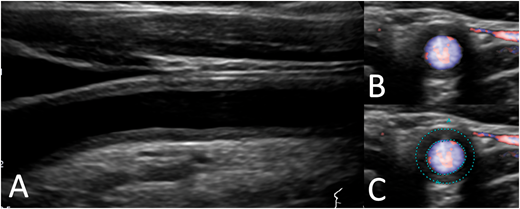

今回は高安動脈炎に特徴的な血管所見に関するClinical PictureがAcceptされました。

タイトルは「Macaroni sign: Takayasu arteritis」です。

掲載雑誌は久々に英国内科学会の発行する内科系雑誌「Quarterly Journal of Medicine(IF 3.1)」です。

高安動脈炎は大動脈に炎症を生じる自己免疫性疾患であり、1908年に高安 右人 先生により初めて報告された疾患です。

20代から40代の若年女性に多く、未だその原因は不明です。

病初期では微熱や倦怠感など不定愁訴様の症状がメインであり診断が難しい疾患です。

その他詳細は成書を参照していただきたいのですが、脈拍の消失や血圧の左右差など特徴的な身体所見が存在し、「脈なし病」とも呼ばれます。

今回高安動脈炎のClinical Pictureについて強調したい点が一つあります。

高安動脈炎の診断が難しい理由の一つに疾患の発見から1世紀が経過した現在でも「特異的な血液検査や抗体検査が存在しない」ことが挙げられます。

身体所見から高安動脈炎を疑った場合には血管造影やCT、MRIなどが有用です。

その中でも頸動脈エコーは侵襲性が低く、今回取り上げた全周性の血管壁肥厚(Macaroni sign)を検出できれば確定診断にぐっと近づきます。

普段の外来で橈骨動脈を両側触知していますか?

ヒントはすぐそこに転がっているかもしれません。